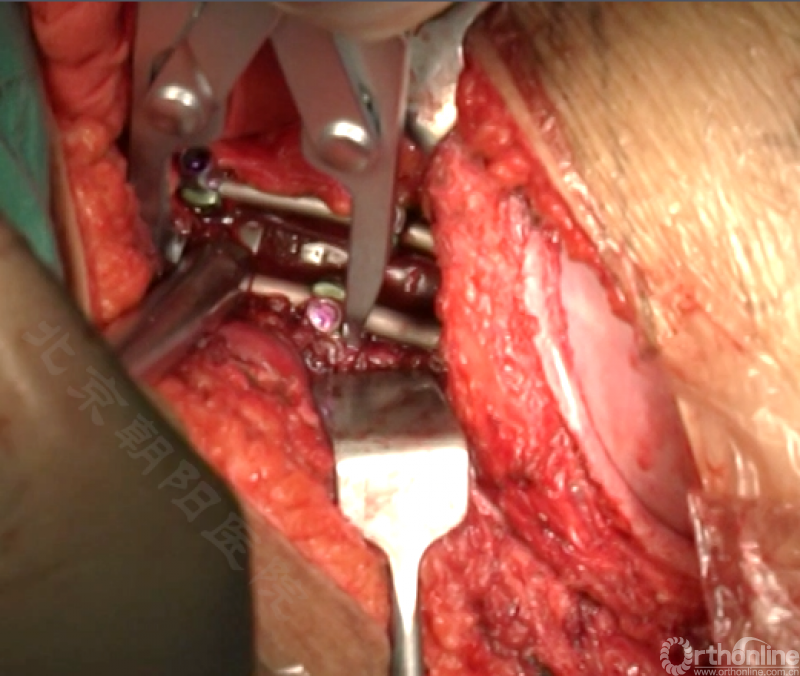

内固定选择的是5.5mm双棒系统,先置入顶椎的螺钉垫板。

置入顶椎的椎体螺钉,螺钉可置入椎体中部到后方1/3之间的范围内。

使用双棒系统时,先置入背侧的螺钉,螺钉指向椎体中线,后置入腹侧的螺钉,螺钉轻度指向后侧。形成对椎体的三角形抓持力。

胸腔侧、腹腔侧螺钉全部置入后,骨移植物植人的越靠近后纵韧带或者纤维环的后缘越好。

将预先折弯的金属棒先置入背侧。

椎间融合器经前方置入凹侧,确保腰椎前凸的恢复和冠状面畸形的矫正,将剩下的骨移植物置入椎间隙内。

置入腹侧金属棒。

使用双棒系统时先安装背侧的棒,可进行90°的去旋转,也可以直接通过前方螺钉矫正冠状面和矢状面的畸形,然后固定后方的棒,可进一步通过加压矫正冠状面畸形。

矫正后神经检测未见异常术中唤醒患者下肢活动良好,术中透视矫正效果满意、内固定位置良好。根据手术具体情况放置合适尺寸的横连接加强内固定。